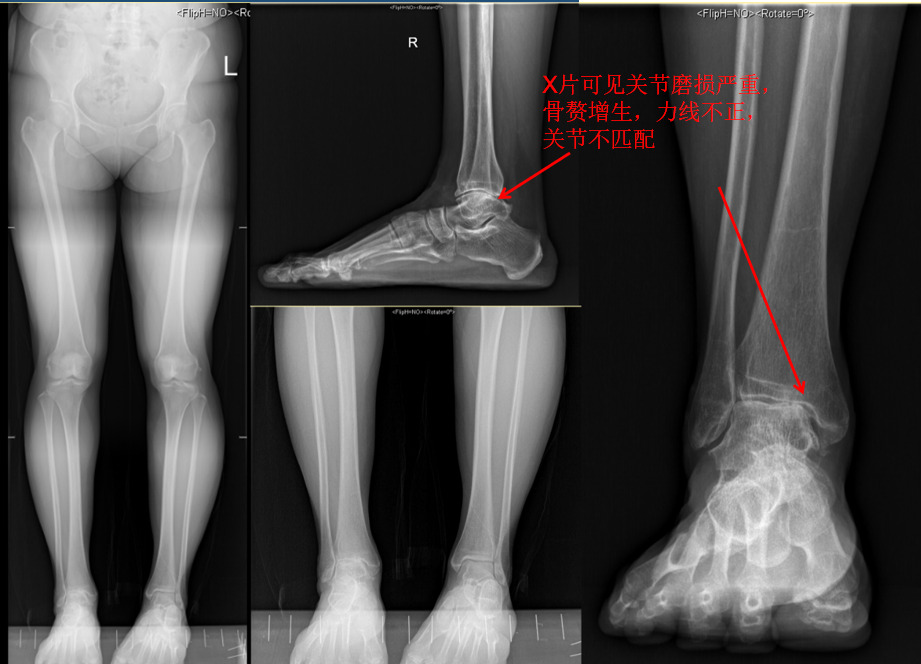

“关节除了骨之外,主要结构还有韧带,类似橡皮筋一样有一定的弹性,同时能保持活动过程中骨的稳定。”宋斌副教授提到,许多人觉得只要骨头没伤到就没啥大问题,把崴脚不当回事。然而,由于韧带损伤在X光片不能直接看到,在临床上往往容易忽视。早期的处理不当,韧带损伤得不到修复,韧带就会出现松弛甚至完全断裂。关节松动了就会出现反复崴脚,出现慢性踝关节不稳,这时就需要手术治疗了。

宋斌:这种认识是错误的。踝关节韧带损伤后最大的危害是引起组成关节的各个骨的互相撞击、碰撞,最终会引起关节内的软骨损伤,而这些软骨损伤是不可逆的,人体不能自行修复,最终会进展为骨关节炎。而关节炎的症状比较重,治疗效果也比较局限,严重降低运动能力和生活水平,所以从长远来说,重视崴脚的治疗从根本上是为了保护关节软骨,延长关节的使用寿命。